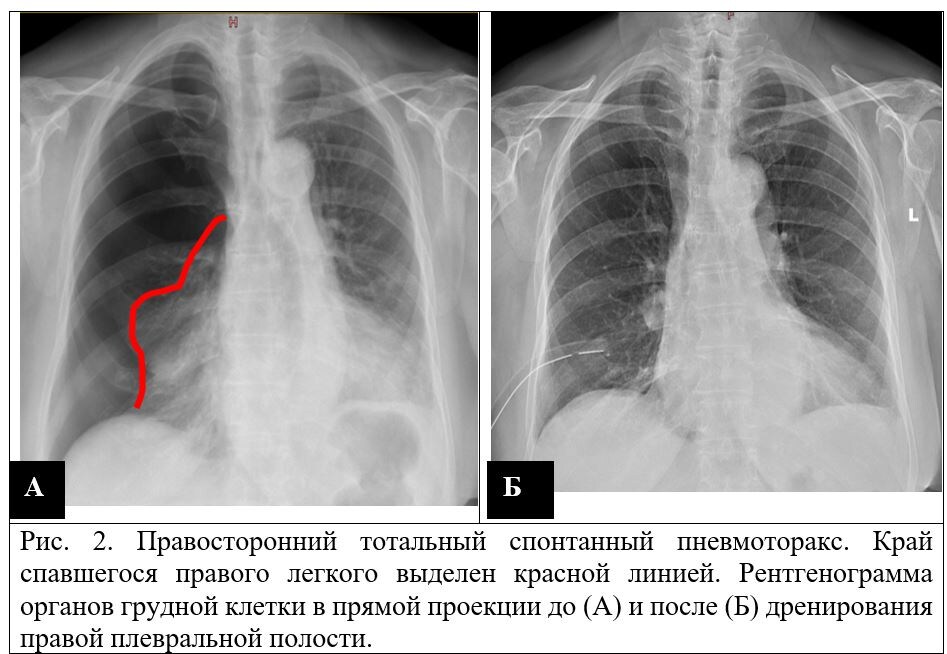

Рентген подтвердил диагноз — тотальный правосторонний спонтанный пневмоторакс, то есть лёгкое полностью спалось.

Под местной анестезией пациенту в плевральную полость установлен дренаж — тонкая трубка, через которую воздух вышел наружу.

Уже на контрольной рентгенограмме лёгкое снова расправилось и начало работать.